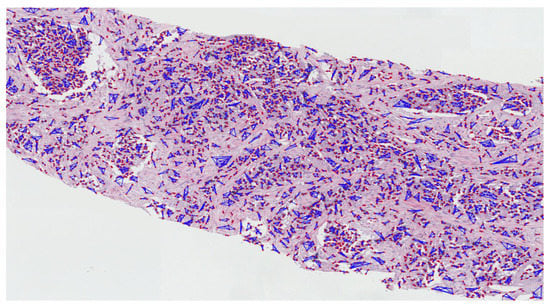

Appendix A

The pathology annotated WSIs used in this research to analyze the pattern and community structure of cell nuclei in grades 3, 4, and 5, shown in Figure A1, Figure A2 and Figure A3, respectively. The cluster analysis was performed successfully on histological images of PCa. For visualization of the community structure of cell nuclei, we plot the clusters in the annotated regions of grade 3, grade 4, and grade 5 in WSIs, shown in Figure A4, Figure A5 and Figure A6, respectively.

Figure A6.

The proliferation and community structure of cell nuclei in the annotated region of grade 5.